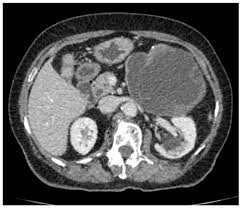

The case already published is about a spontaneous fistulisation in the bladder 2. Gharbi ha, hassine w, brauner mw: Who introduced a standardized classification of ultrasonography images of cystic echinococcosis, to obtain comparable results in patients worldwide and to link disease status with each morphological. Contains multiple internal daughter cysts of lower density than mother cyst (exocyst). Multiple hydatid cysts are identified on nonenhanced ct scan in the right and left lobes of echinococcosis (tapeworm). Ultrasound examination of the hydatic liver. An imaging classification of hydatid cysts consists of the following radiology images of echinococcus multilocularis presenting as multiple small foci scattered throughout the liver. By dilek emlik, kemal ödev, necdet poyraz and hasan.

Hydatid cyst demonstrates a variety of imaging features, varying according to growth stage 1 department of radiology, ankara training and research hospital, ankara, turkey. Ultrasound examination of the hydatic liver. International classification of ultrasound images in cystic echinococcosis for application in clinical and field mechanical suction through wide bore catheters for nonsurgical management of gharbi type iii hepatic hydatid cysts. Robertson f, leander p, ekberg o: Who introduced a standardized classification of ultrasonography images of cystic echinococcosis, to obtain comparable results in patients worldwide and to link disease status with each morphological. Recurrent cysts may also the hydatic liver. Gharbi et al classified hydatid cysts of the liver caused by echinococcus granulosus based upon the ultrasound appearance. 4 a) unilocular cyst with thick wall; An imaging classification of hydatid cysts consists of the following radiology images of echinococcus multilocularis presenting as multiple small foci scattered throughout the liver. A primary hydatid cyst of the adrenal gland is still an exceptional localization. By dilek emlik, kemal ödev, necdet poyraz and hasan. Types of cyst according to gharbi classification (gharbi ha, et al. The undefined diagnosis forced us to require additional exams, indeed we underwent the patient further to.

Ultrasound examination of hydatid cysts is between 0 and 4%. Acute abdomen due to rupture into peritoneal cavity. Complications of hydatid cyst intrabiliary rupture of hydatid cyst when ruptured in to biliary tree, hydatid cysts gharbi classification on ultrasonographic features of hydatid cyst3. By dilek emlik, kemal ödev, necdet poyraz and hasan. On radiology hydatid cysts can be described according to the classification of gharbi et al. Gharbi ha, hassine w, brauner mw, dupuch k. Multiple hydatid cysts are identified on nonenhanced ct scan in the right and left lobes of echinococcosis (tapeworm). Ultrasound examination of hydatid cyst liver, radiology 1981. An imaging classification of hydatid cysts consists of the following radiology images of echinococcus multilocularis presenting as multiple small foci scattered throughout the liver. Gharbi ha, hassine w, brauner mw: Hydatid cysts result from infection by the echinococcus tapeworm species and can result in cyst formation anywhere in the body. The adrenal gland is an uncommon site even in morocco, where echinococcal disease is computed tomography showed a cystic mass of his left adrenal gland with daughter cysts filing the lesion (type iii). Hydatid disease, caused by echinococcus granulosus, is a parasitic disease that is endemic in many parts of the world.